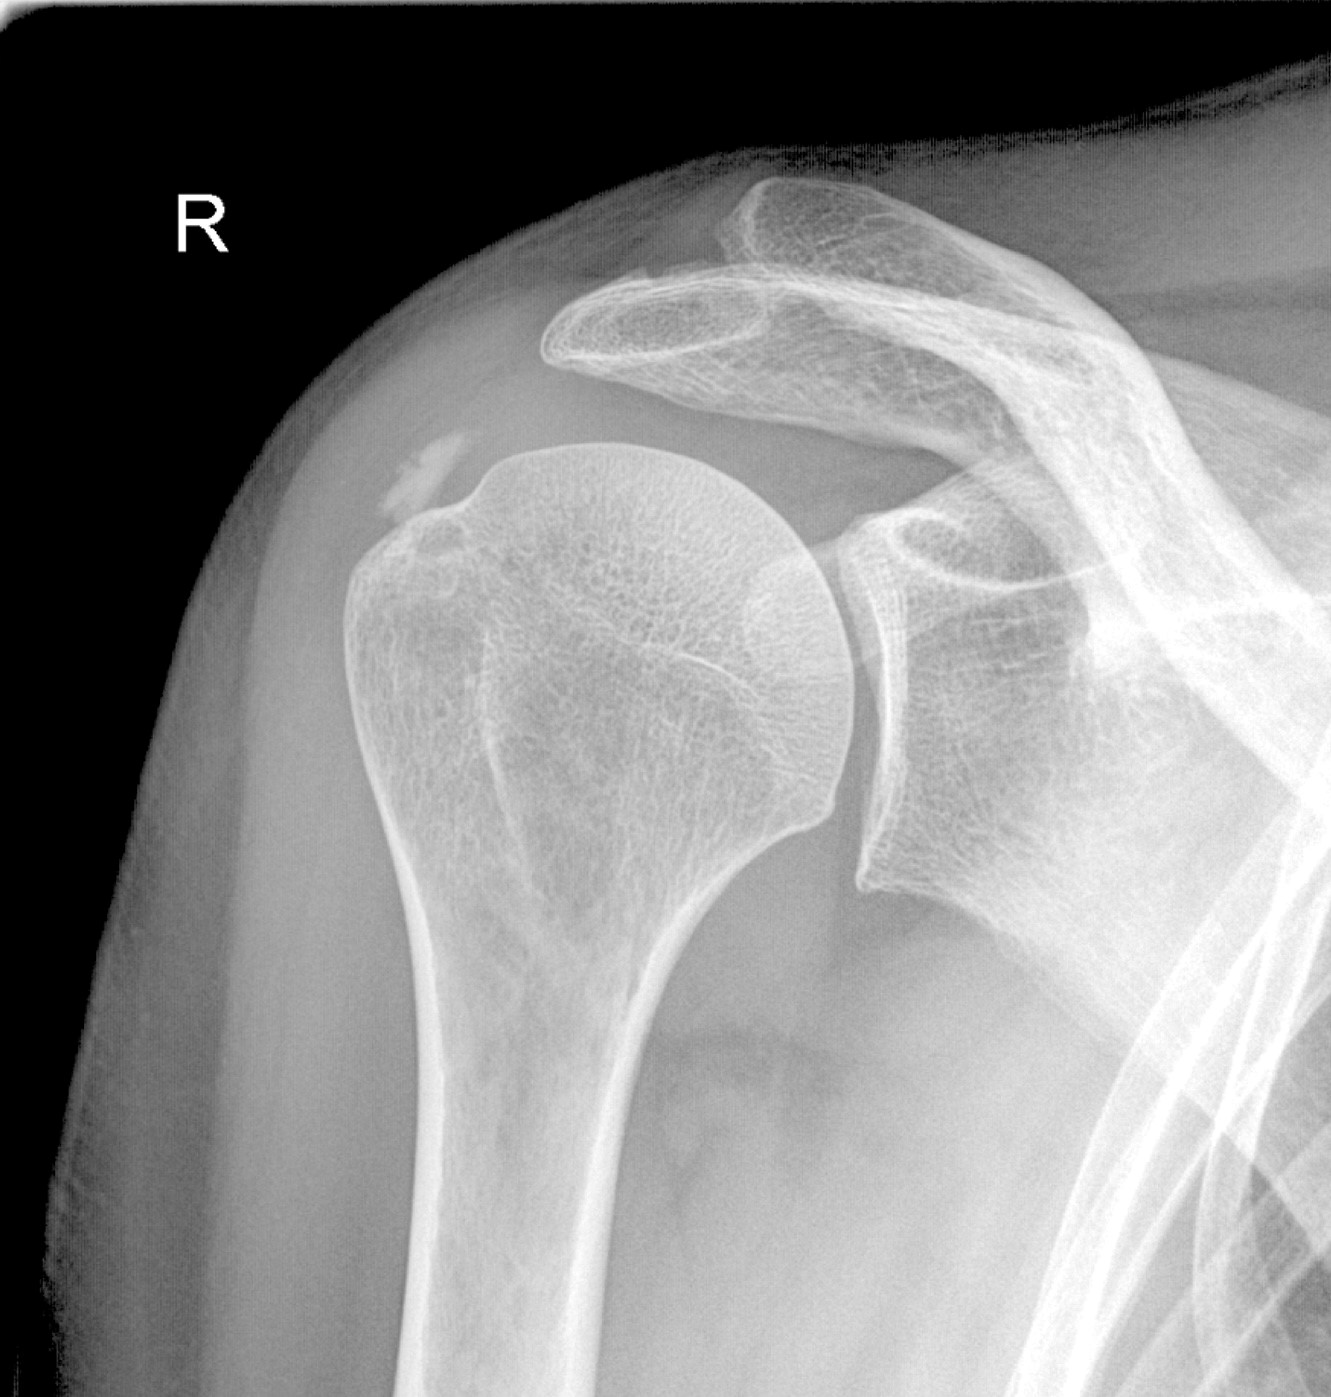

Plötzliche Schulterschmerzen, vor allem beim Heben des Arms oder nachts, deuten häufig auf eine Kalkschulter (Tendinosis calcarea) hin – eine Ablagerung von Kalzium in den Sehnen. Die Beschwerden reichen von dumpfem Druck bis zu akuten Schmerzattacken und können zu erheblichen Einschränkungen im Alltag und Sport führen, aber auch im Wohlbefinden.